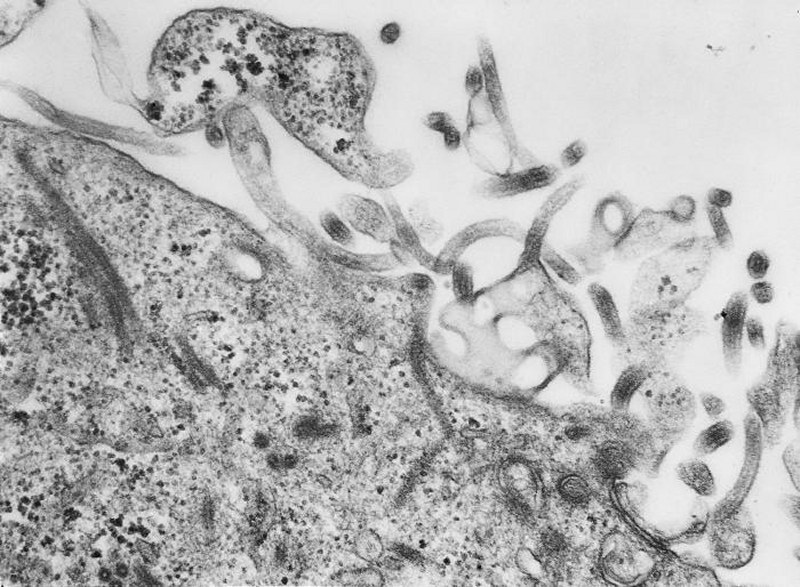

Ebola Haemorrhagic Fever

Ebola Attributes

Ebola Pictures